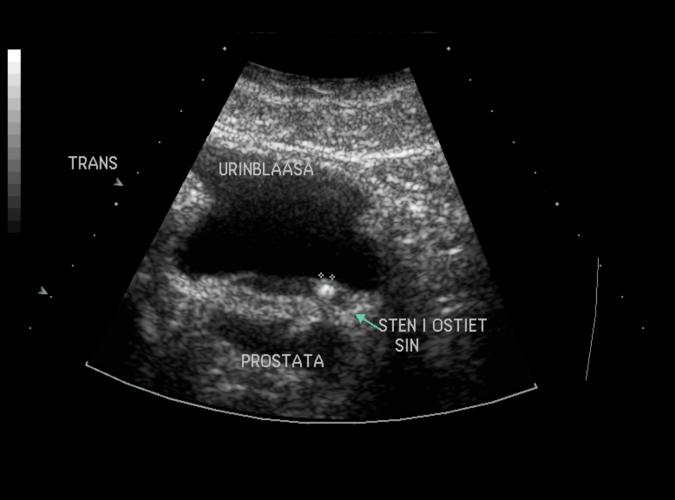

Trotts en normal vänster njure, påvisas ultraljud ett konkrement in till vänstra ostiet.

Trans.urinblåsa. Samma patient som i 9u